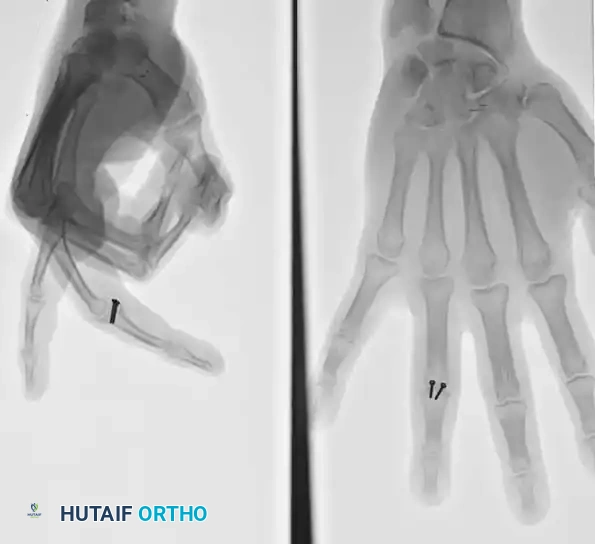

Open Reduction and K-Wire Fixation: The Pratt Technique

For transverse or short oblique fractures where screw fixation is impossible, the Pratt technique offers a reliable method of crossed K-wire fixation.

Step-by-Step Technique:

* Expose the extensor tendon and incise it longitudinally precisely in its center. Retract it to each side to expose the fracture site.

* Drill a K-wire into the distal fragment under direct vision.

* After anatomically reducing the fracture, drill the wire retrograde into the proximal fragment.

* Repeat with a second wire to create a crossed configuration, ensuring rotational stability.

* Correct any rotational deformity (scissoring of the digits). Note that while some minor shortening may be acceptable, malrotation is poorly tolerated and leads to digital overlap during flexion.

* Meticulously repair the extensor tendon with a fine non-absorbable or slowly absorbing suture.

* Support the finger in the position of function (MCP flexed 70 degrees, PIP extended) and the wrist in 30 degrees of extension.